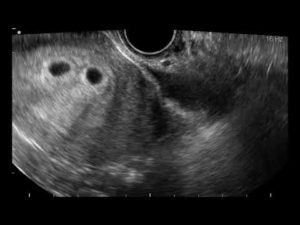

Фото УЗИ двойни на ранних сроках беременности, 8 недель

В 8 акушерских недель (или 6 недель от момента зачатия) обычно используют трансвагинальный способ УЗИ. Аппарат вводят внутрь, чтобы лучше разглядеть эмбрионы. На мониторе видны два или три темных пятна. Врач измеряет длину зародышей и фиксирует несколько сердцебиений.